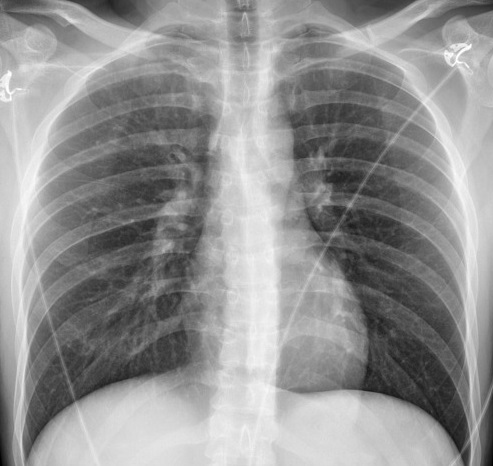

Image radiologique PA

d'une fracture du sternum . Il est très difficile de

determine , evaluer et d'analyser l'emplacement de

la lésion fracturaire |

Même cas sur profile gauche . Aspect

lesionaire du fracture est la deplacement

fragmentaire claire du cortex et de la perios

anterieure du sternum ( pic ) |